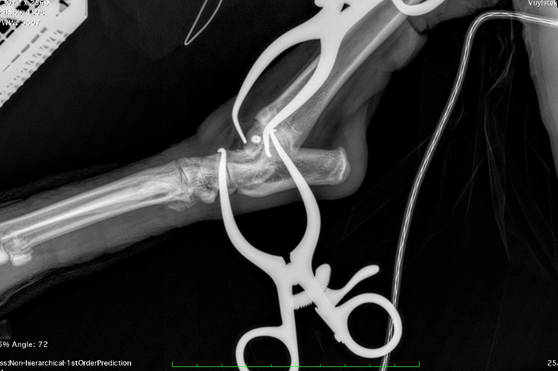

The fracture’s small size, delicate location, and proximity to the joint meant precision was critical. To ensure accurate screw placement, Mark performed the surgery under real-time intra-operative imaging—a technique he has refined over more than a decade. Using continuous X-ray guidance allowed confirmation of ideal screw trajectory and depth, avoiding both joint violation and inadequate fracture engagement.

Instead, Mark and the team opted for an innovative solution: a headless compression screw (HCS), commonly used in human orthopaedic surgery for peri-articular fractures. The HCS generates compression along the fracture line thanks to its differential thread pitch, while its headless design allows full burial within the bone—eliminating the risk of joint interference.